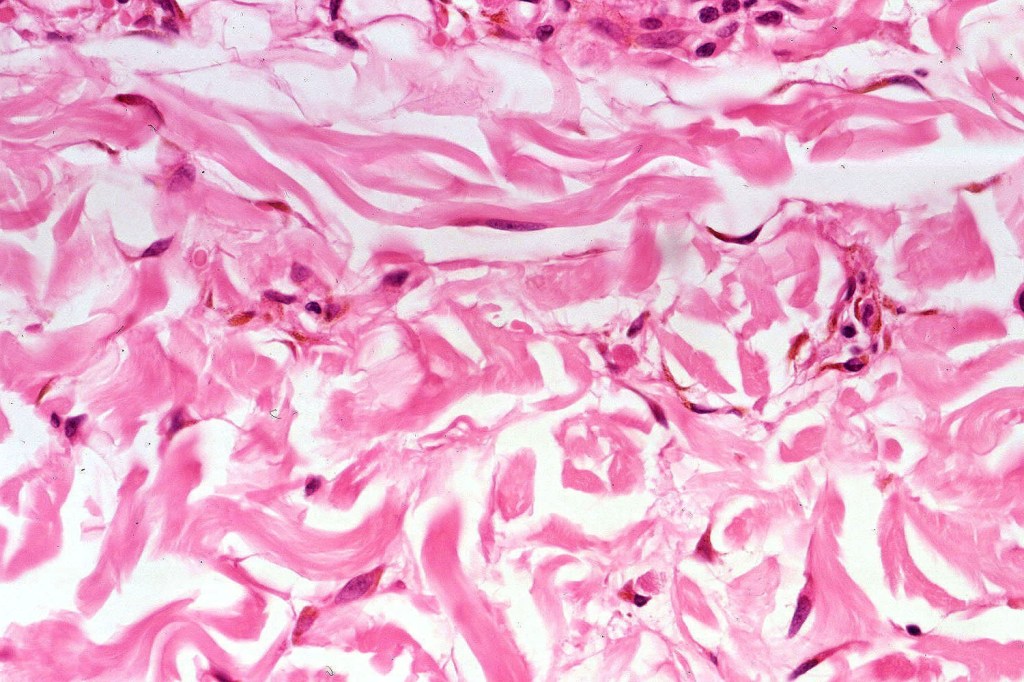

•Admixture of spindle cells, pigmented bipolar or dendritic cells & melanophages

•Cytoplasm is pale and nuclei are small with inconspicuous nucleoli

•Stromal fibrosis, myxoid change, vascular hyalinization with cyst formation are often seen

•Some tumors are composed spindle cells in a fascicular or neuronevoid pattern